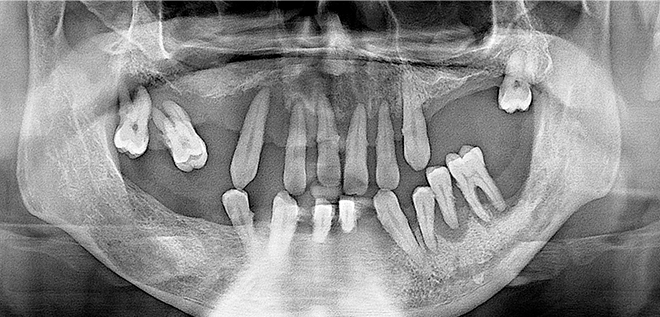

• 01

3D CT시스템을 이용한 정밀진단

3차원 CT장비로 촬영 후 잇몸뼈의 상태 및 신경구조의 미세한 부분까지 진단합니다.

Before & After

어려운 임플란트 시술도

남양바른탑에서는 가능합니다.